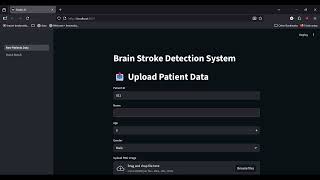

Medical Image Management System for Brain Stroke Analysis by Ashwin Linson

This project is a lightweight medical image management application designed to handle patient information and associated clinical images in a structured and user-friendly manner. The system currently focuses on providing an intuitive interface to store, view, search, and manage patient metadata along with uploaded CT scan images (PNG/DICOM).